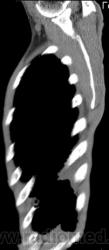

На фоне консолидации полость без содержимого. Может быть всё что угодно, что сопровождается деструкцией. Нужны ещё томограммы в лёгочном окне.

Изображения выставлены все. Ваше мнение уважаемые коллеги?

Это КТ 2-летней давности и попало оно мне в руки, после недавнего прохождения контроля пациентом, когда мы стали перед вопросом о специфическом / не специфическом процессе.

Тогда, пациента 2 месяца лечили от пневмонии, лечили интенсивности, стационарно, в серьёзном учреждении.

6 и 9 срезы.

Предположу аспергиллез